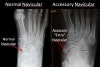

Foot DP, lateral, oblique view를 촬영합니다.

X-ray : 부주상골 증후군(Accessory navicular)